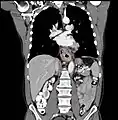

Additional testing is needed to assess how much the cancer has spread (see #Staging, below). Computed tomography (CT) of the chest, abdomen and pelvis can evaluate whether the cancer has spread to adjacent tissues or distant organs (especially liver and lymph nodes). The sensitivity of a CT scan is limited by its ability to detect masses (e.g. enlarged lymph nodes or involved organs) generally larger than 1 cm.[41][42] Positron emission tomography is also used to estimate the extent of the disease and is regarded as more precise than CT alone.[43] Esophageal endoscopic ultrasound can provide staging information regarding the level of tumor invasion, and possible spread to regional lymph nodes.

Contrast CT scan showing an esophageal tumor (coronal view)